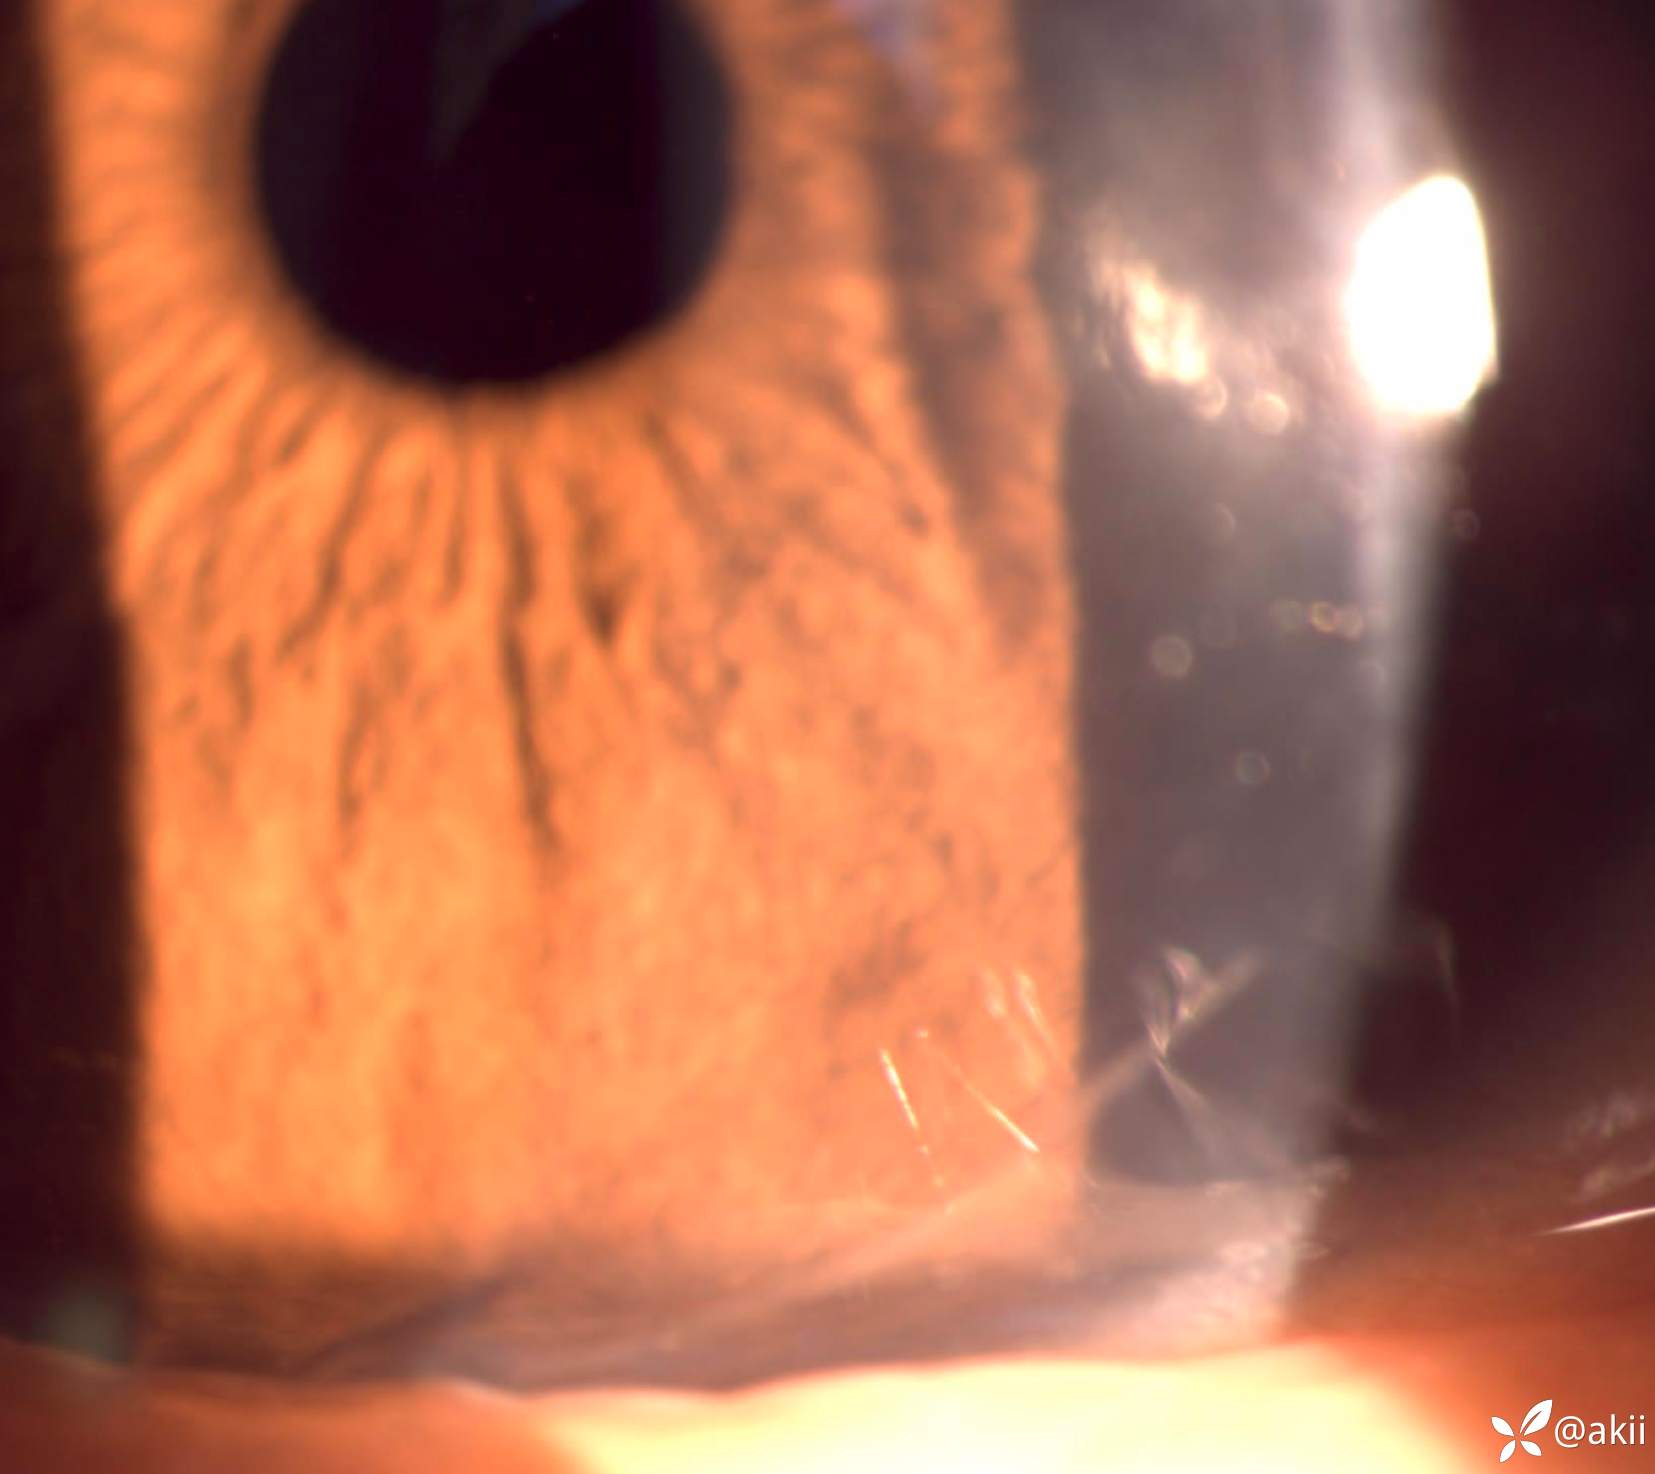

白内障病人,既往角膜外伤致不规则散光。行白内障手术+散光松解,术中局部可疑后弹力层脱离,前房留小气泡并缝线1针。

拆线后即刻地形图,角膜散光明显减少

拆线前后散光变化3.6D,中央3mm变化更明显

所以,角膜缝线是可以极大改变角膜形态和矫正视力。如果影响视力,在允许的情况下尽早拆线会好一些。

反之,如果角膜有明显散光,除了LRI或AK之外,也可以在平坦轴位缝线改变散光,该方式李绍伟在公众号有病例是这么处理的。